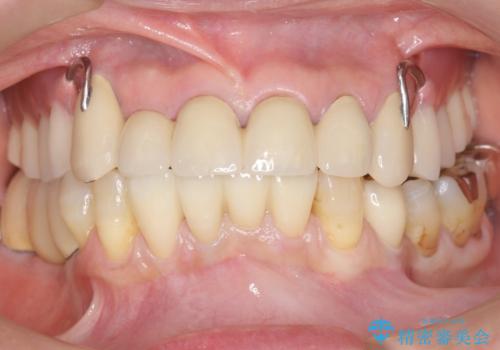

自然な仕上がりに喜んで下さいました。

クラウンを連結することにより気にされていた動揺もなくなり、安心して頂けました。

被せ物の種類:オールセラミッククラウン スタンダード